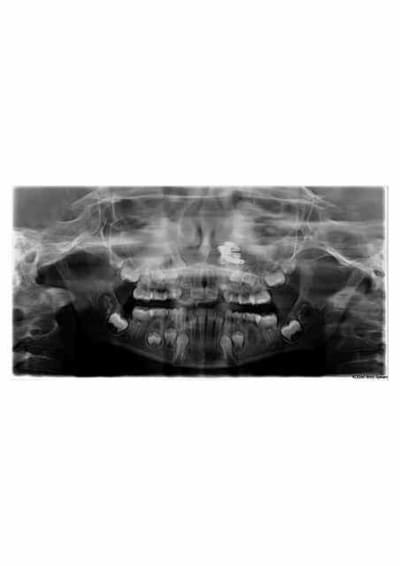

patiente de 9 ans venue pour un trt odf

pano effectuée dans la foulée et là.......surprise.

j'ai demandé un scanner pour mieux visualiser en 3D.

qu'en pensez-vous?